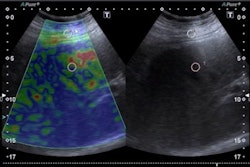

Dr. Davide Negroni presents findings from research he led on combining SMI with elastosonography for diagnosing thyroid lesions. While the method's diagnostic performance was lower than ACR TI-RADS when used in a heterogeneous, it may yield some potential.SMI helps visualize low velocity and microvascular flow by using a clutter suppression algorithm. From there, it provides color overlay images, with previous studies suggesting it can provide additional value over conventional color or power Doppler imaging. Elastography meanwhile measures stiffness of tissues, with harder tissues indicating potential malignancies.

The researchers found that area under the curve (AUC) values favored ACR TI-RADS over SMI, elastography, or combined SMI and elastography.

| Diagnostic performance on thyroid nodules (AUC) | |

| ACR TI-RADS | 0.673 |

| SMI plus elastography | 0.616 |

| SMI | 0.576 |

| Elastography | 0.576 |

By combining all three standalone methods, the AUC improved to 0.699. Additionally, owing to elastography, solid nodules on thyroid findings appear at greater risk of malignancy, Negroni said. He added that no specific vascular patterns at SMI of evolving lesions were identified.